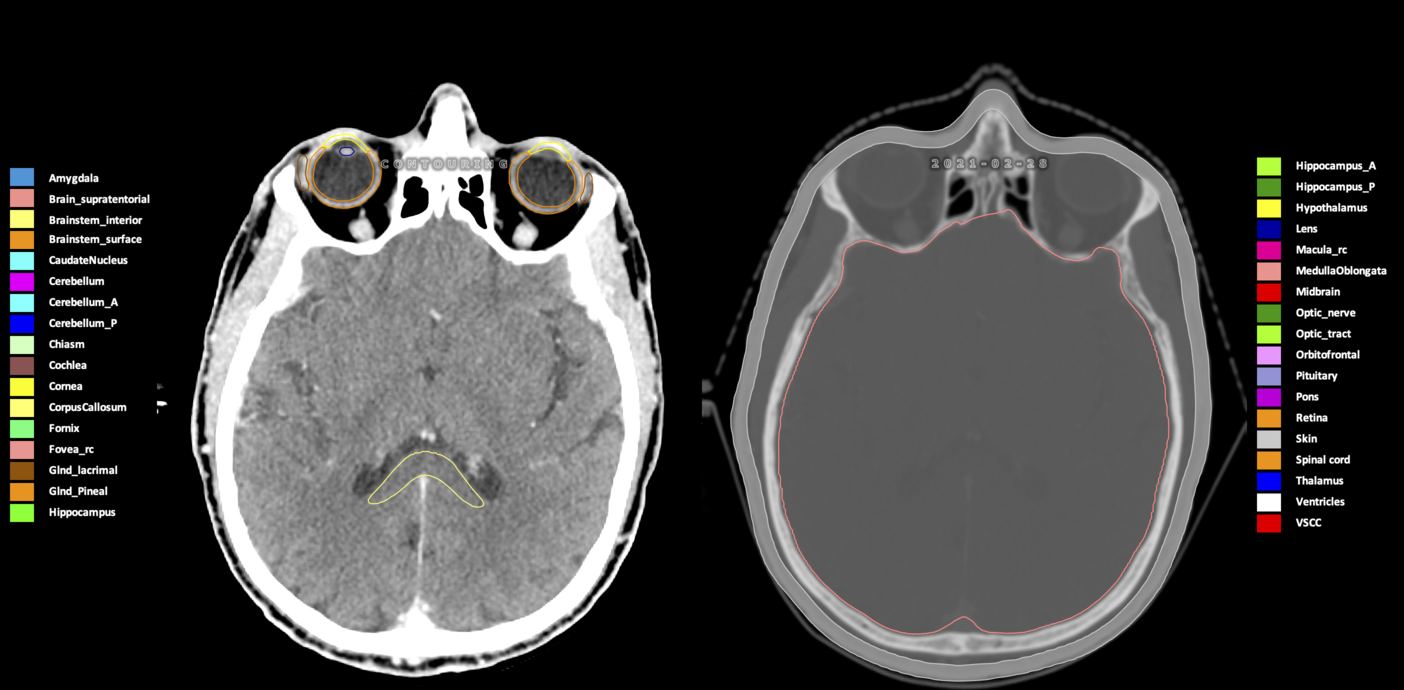

Included are all OARs known to be relevant for radiation-induced toxicity in neuro-oncology: brain, brainstem (midbrain, pons, medulla oblongata), chiasm, cerebellum (anterior & posterior), cochlea, cornea, hippocampus (anterior & posterior), hypothalamus, lens, lacrimal gland, optic nerve, pituitary, skin, and vestibular & semicircular canals. To further facilitate research on cognition, vision and radiological changes after irradiation of the brain, potential clinically-relevant OARs are included: amygdala, caudate nucleus, cerebellum (anterior & posterior), corpus callosum, fornix, macula, optic tract, orbitofrontal cortex, periventricular space (PVS), pineal gland, and thalamus.

Three-dimensional delineation of the 25 consensus OARs for neuro-oncology are shown on CT (WW/WL 120/40, 3000/600), 3T MR images, (T1Gd, T2FLAIR 1mm) and 7T MR (MP2RAGE 0.7 mm). All are presented in transversal, sagittal and coronal view.